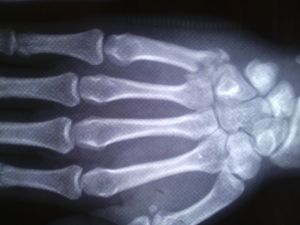

掌骨幹骨折

多由直接暴力如打擊或擠壓傷所造成,可以為單一或多個掌骨骨折。骨折類型以橫斷和粉碎者多見,因扭轉和間接暴力亦可發生斜形或螺鏇形骨折。由於屈指肌和骨間肌、蚓狀肌的牽拉,骨折向背例成角。對於掌骨幹穩定性骨折,通過手法復位後,可用小夾板外固定。在臂叢神經阻滯麻醉下,在碗關節輕度背伸下,牽拉患指,糾正重疊畸形,術者在掌骨骨間隙擠壓並糾正其側方移位,最後屈曲掌指關節,用拇指置於手掌推擠掌骨頭及骨折遠端向背側,其他四指置於手背骨折的近側段,以糾正向背成角畸形,如果穩定,可以使用支具固定,一般固定4—6周,但要每周複查X線片,如有移位需手術切開。對閉合性不穩定性掌骨幹骨折、多發掌骨幹骨折或手部腫脹嚴重的穩定性骨折以及開放性骨折,為了使其能早期進行功能練習,防止關節僵硬,以切開復位、內固定為宜。開放性骨折的內固定主要選用克氏針內固定,從掌骨頭打人,為了加強其穩定性還加用1根克氏針橫行固定相鄰掌骨的遠側部分,即可防止鏇轉畸形,並維持遠側掌橫弓,對於第二、三學骨,因腕掌關節基本上無活動,因此縱行克氏針可固定至其近端之腕骨。若第二至五掌骨均有骨折,其橫行固定之克氏針要用兩根,才能維持掌橫弓。閉合性拿骨幹骨折切開復位時,單個掌骨骨折用縱s形切口,而多個掌骨骨折時用橫S形切口或兩個縱形切口。切開皮膚後注意保留兩根手背淺靜脈,以免術後患手腫脹。內固定器材可選用微型鋼板、克氏針或鋼絲等。